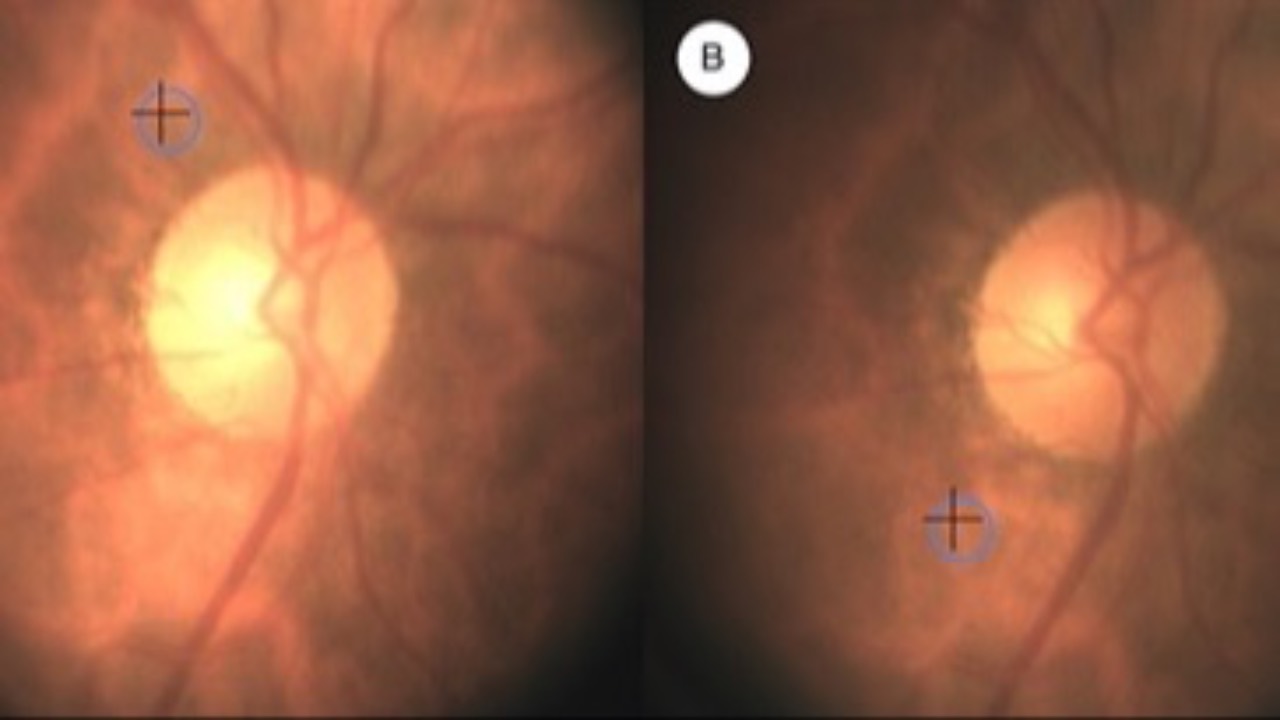

Retinal O2 Saturation & Glaucomatous VF Defects

The Journal of Glaucoma recently published findings which found a counterintuitive relationship but significant correlation between retinal oxygen saturation (StO2) and the severity of visual field loss in glaucoma patients.

A study utilizing novel diffuse reflectance spectroscopy found higher...